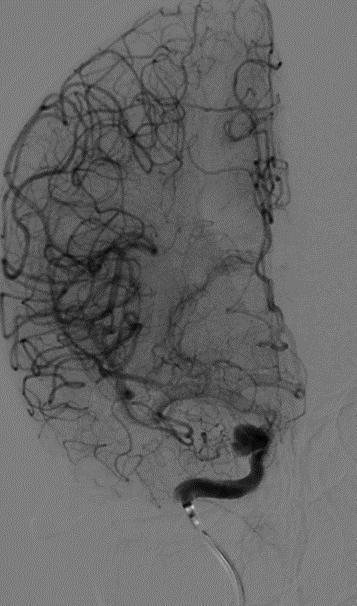

入院后行全脑血管造影证实右侧颈内动脉眼段动脉瘤。瘤颈宽约4.91mm,瘤体最大径约8.21mm,载瘤动脉远近端血管直径分别为3.07mm、3.52mm。

术前造影:

正侧位造影示动脉瘤内造影剂明显滞留,载瘤动脉通畅,血流导向作用显著。

术后即刻: